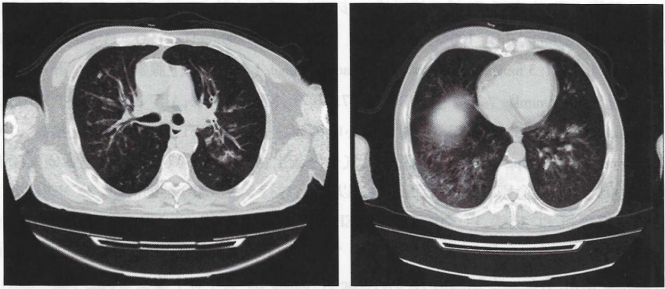

患者入院8 d前清理老宅后出现咳嗽、咳痰,为黄色黏痰,偶带血丝,伴气喘、发热,最高体温38.5℃;无流涕、胸痛,无心悸。于当地医院就诊,查血常规:WBC 5.61×109/L,NEU% 83.8%;PCT 0.3 ng/ml;CRP 158 mg/L;胸部CT:双肺支气管管壁增厚,局部管腔狭窄,远端肺组织可见结节斑片状高密度及磨玻璃样改变,双下肺为著(图1)。予抗感染、平喘、纠正电解质紊乱等对症处理(具体用药不详),咳嗽、呼吸困难进一步加重。入院2 d前至我院急诊科就诊,查血气分析(储氧面罩15 L/min):pH 7.304,PaCO2 33.9 mmHg,PaO2 169 mmHg,HCO316.3 mmol/L,SaO98%,cLac 1.9 mmol/L。血常规:WBC 11.43×109/L,NEU% 89.6%;PCT 2.19 ng/ml。呼吸困难进一步加重,为进一步诊治收入我科。

图1  入院前胸部 CT

注:双肺支气管管壁增厚,局部管腔狭窄,可见树芽征,远端肺组织可见结节斑片状高密度及磨玻璃样改变,双下肺为著。